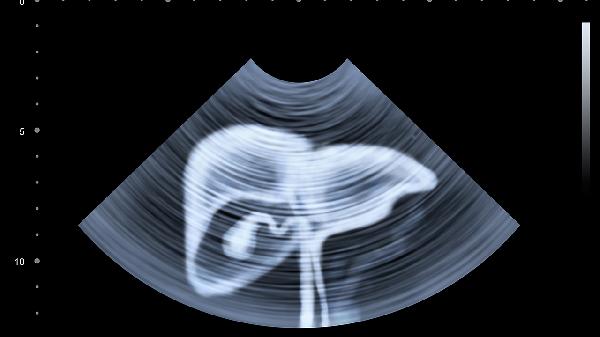

发现腹部淋巴结肿大应及时就医检查,通过超声、CT等影像学检查明确肿大性质。日常应注意观察症状变化,避免剧烈运动导致淋巴结区域不适。饮食宜清淡易消化,保证充足营养支持免疫系统功能。保持规律作息,避免过度劳累,有助于身体恢复。若伴随发热、消瘦等全身症状更应尽早就诊。